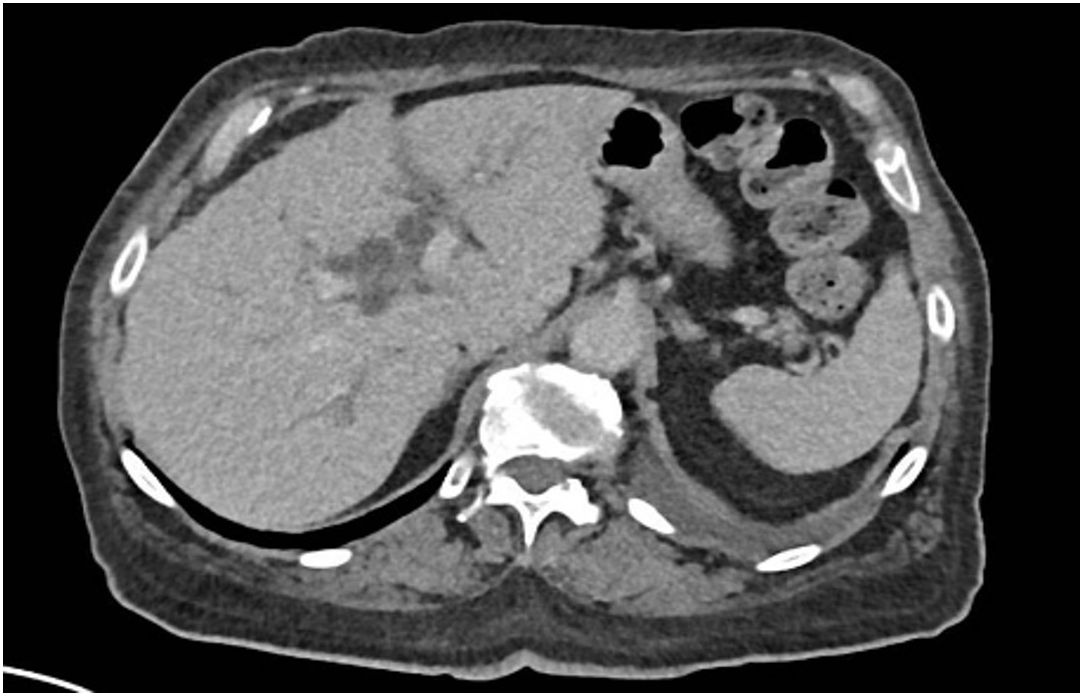

Laboratory investigations showed hemoglobin of 5.8 g/dL, 3.5% schistocytes, undetectable haptoglobin, and severe thrombocytopenia (20,000/mm³), consistent with thrombotic microangiopathy (TMA). Liver enzymes were elevated (Alanine transaminase 302 U/L, Aspartate transaminase 300 U/L, alkaline phosphatase 378 U/L, GGT 302 U/L), as well as Creatine phospho-kinases (1,259 U/L) and troponin-T (145 U/L). Creatinine had risen from 0.8 to 1.6 mg/dL. CT scan showed moderate bilateral pleural effusions and mild intrahepatic bile duct dilatation, without clear evidence of progression (Figure 3). Fundoscopy revealed grade 3 hypertensive retinopathy. Cardiac MRI and echocardiography showed preserved function and no signs of myocarditis.

Figure 3

Moderate pleural effusions and mild intrahepatic bile duct dilatation, without clear evidence of progression on Computed Tomography Scan.